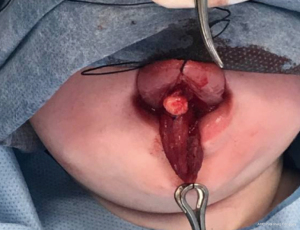

A total of five cases of head and neck FDCs were identified in the last 10 years at RCH. These are identified in Table 1. The mean age at diagnosis was 8.2 months. Two were female and three were male. Two cases were found in the floor of mouth (FOM), two in the base of tongue (BOT) and one in the uvula. Magnetic resonance imaging (MRI) was utilised in two cases (Figure 1), ultrasound (US) in one and two had no imaging. Four cases were treated with primary excision (Figure 2). One case in the FOM had attempts at excision, aspirations and sclerotherapy with definitive excision following. This patient had two previous attempts at sublingual gland excision at another site after initial presentation at four months of age. Following recurrence after attempted aspiration, he was referred to the RCH for further management. A multi-disciplinary meeting suggested possible lymphovascular malformation and so a decision for sclerotherapy was made. The cyst was injected with 100 mg of doxycycline under US guidance at 6 months of age. Despite this, the cyst recurred and definitive transcervical excision was performed at 8 months of age. Four cases had enteric epithelium found on histopathology, and one respiratory alone. Following excision, there was no reported recurrence of FDC, with three of five cases having a follow-up of over two years. Two cases did not report follow-up in the EMR as they were followed up privately.

| 5 | 8 | M | FOM | Feeding difficulty | MRI: T2 and T1 hyperintense | Multiple excisions and aspirations, and attempt at sclerotherapy | Enteric FDC and dermoid cyst | Residual cyst, nil recurrence at 6 months post excision |